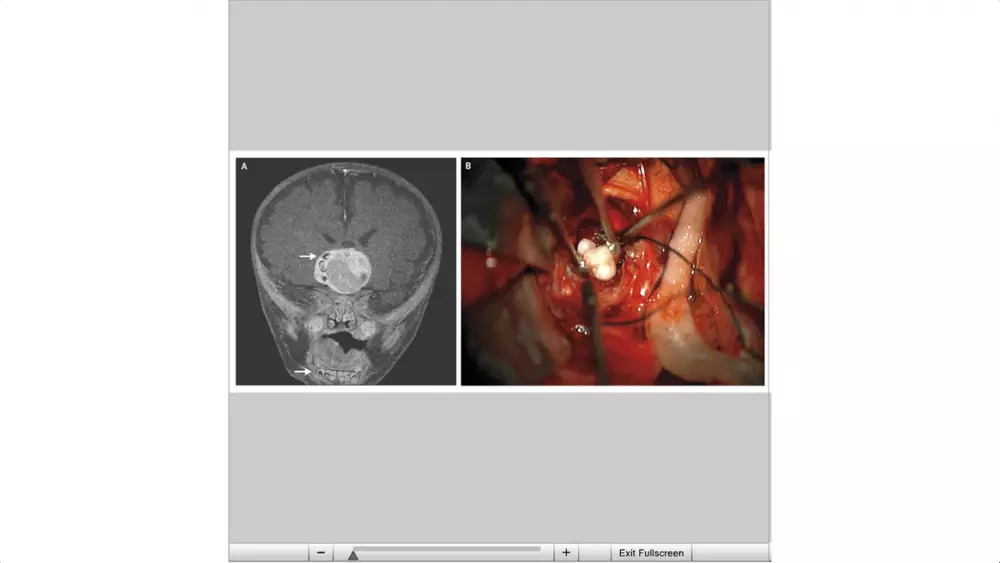

Нейрохирурги одной из клиник в американском штате Мэриленд удалили несколько зубов из мозга четырех-месячного мальчика. Во время магнитно-резонансной томографии головы у ребенка обнаружили большую опухоль, внутри которой и сформировались зубы. Уникальный случай, возможно первый в мире, описан в научном журнале New England Journal of Medicine. Как рассказали врачи, речь идет о редком типе опухоли - краниофарингиоме или опухоли кармана Ратке. Это врожденное новообразование центральной нервной системы встречается в среднем 1-2 раза на один миллион человек. Операция прошла успешно. Маленький пациент в настоящее время проходит курс реабилитации и гормонозаместительной терапии. Без хирургического вмешательства мальчик бы не выжил.